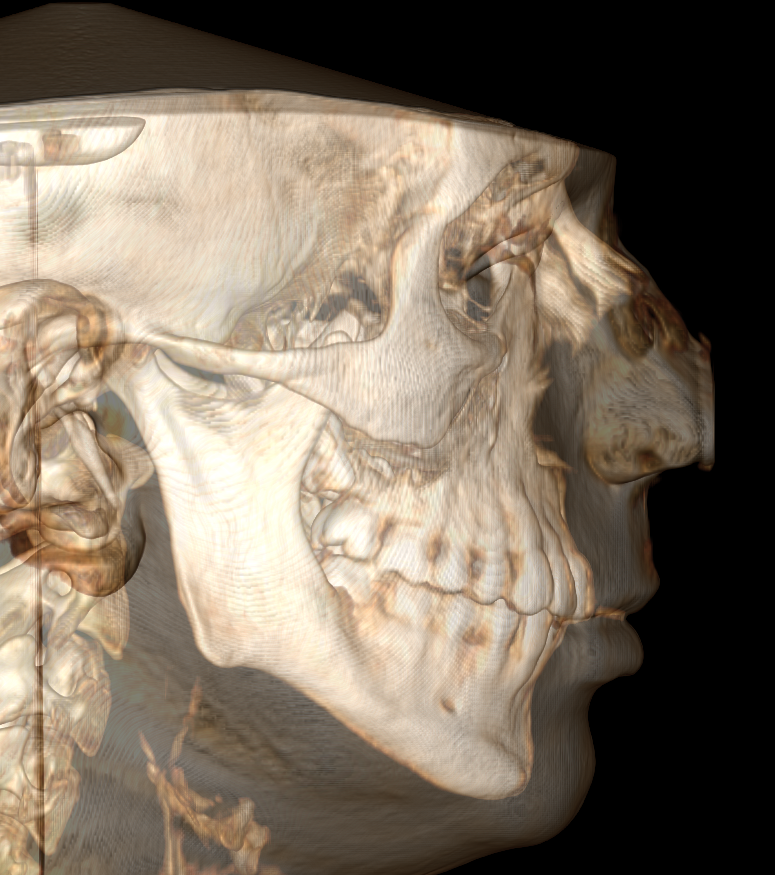

CBCT (Front + Side) + OPG (Old Before & New After braces) (need decompensation)

My Analysis (Based on CBCT):

- Face Type: High divergence, nasolabial folds, poor midface & infraorbital support)

- Bimax (BSSO + Lefort 1) with CCW Rotation: I need to close that 132° angle and get projection.

- Midface support: I’m leaning towards custom PEEK inframalar/infraorbital implants but I want to know if I can avoid paranasal implants by performing a High LeFort I cut and advancing the ANS, or maybe eventually both?

- Genioplasty: Undecided. If the CCW rotation provides enough projection, I might skip it, but idk tbh.